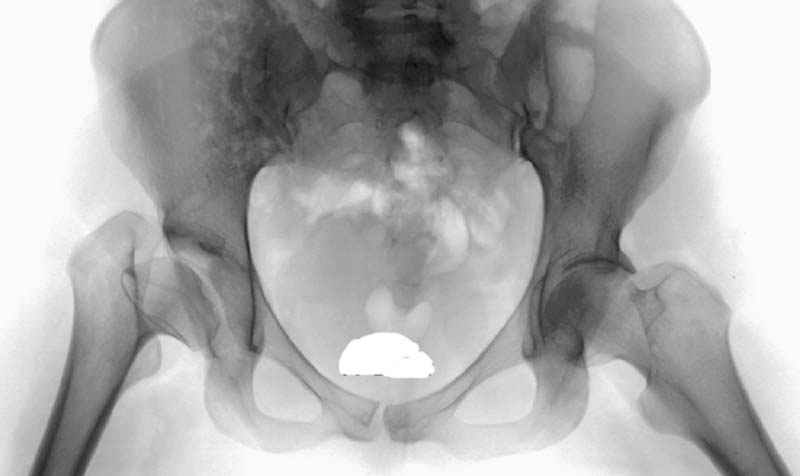

Модель несовершенна, согласен, однако я экспериментировал и с импровизированной илеофеморальной связкой и ацетабулярной губой. Результат был тот же, подвижный узел замыкался посредством аналога СГБ. Для интереса я прилагаю фото., где сымитированы наружные связки и вертлужная губа, но без СГБ видно по показаниям динамометра, что данные структуры незначительно только на 0.5 кг разгружают аналог отводящих мышц. Почему модель получилась именно такой можно рассказать и подробнее если захотите…